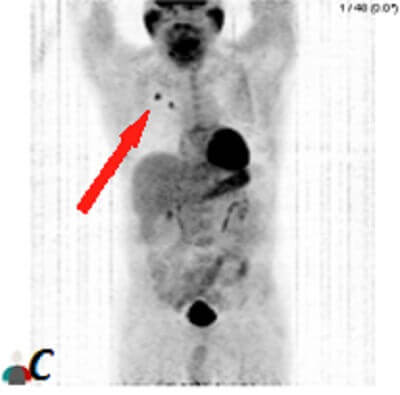

Diagnosis: Metastatic lung cancer to the cerebellum

Figure 1: Red arrow (a) and (b) Axial T1 post contrast and FLAIR images demonstrate a circumscribed intra axial enhancing mass in the left cerebellar hemisphere with surrounding vasogenic edema abutting the fourth ventricle. (C) 3D rotational MIP from a PET-CT scan demonstrates hypermetabolic right upper lobe pulmonary nodules consistent with lung cancer (in this case non small cell).